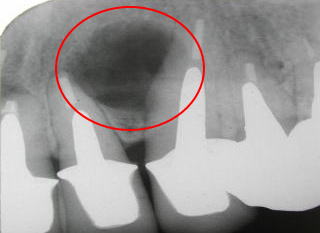

根の先が化膿して、レン

トゲンで黒くなっているの

がわかります。

レントゲンで歯の根の先が化膿しているのが発見されることはよくあることです。

この病気(根尖病巣)はゆっくりと進行するので、化膿の範囲が小さい時は急いで治療する必要は

ありません。

虫歯と同様、進行しているのか進行が止まっているか見極めてから治療すればよいです。

ただ大きくなると手術になってしまうこともありますので、定期的に大きさをチェックする必要が

あります。

痛みや腫れが生じたり、レントゲンで進行しているのが確認された時が治療時期といえます。